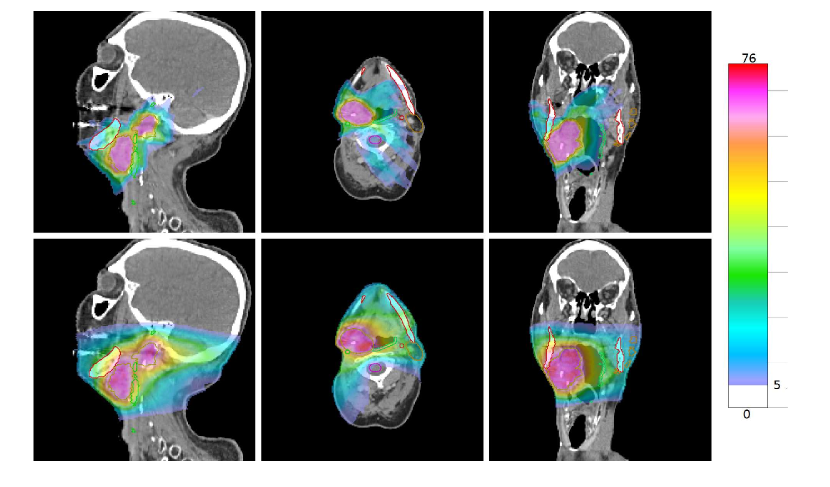

Our goal in this section is to demonstrate that the group sparsity approach is now practical for non-coplanar IMRT — the runtimes are reasonably fast and the dosimetric quality is superior to that of the clinical plans we compare against. Figures 1 and 3 (top rows) show sagittal, transverse, and coronal views for non-coplanar treatment plans created for the cases “H&N” and “LNG#1” using 202020 non-coplanar beams selected from 811811811 and 553553553 candidate beams, respectively, by our group sparsity approach. Clinical plans for each case are shown in the bottom rows. Corresponding dose-volume histograms for these cases are shown in figures 2 and 4.

Figure 1: Plans created for case “H&N”. The group sparsity plan is shown in the top row, and the clinical plan is shown in the bottom row. Dose below 5 Gy is not shown.

Figure 3: Plans created for case “LNG#1”. The group sparsity plan is shown in the top row, and the clinical plan is shown in the bottom row. Dose below 5 Gy is not shown.